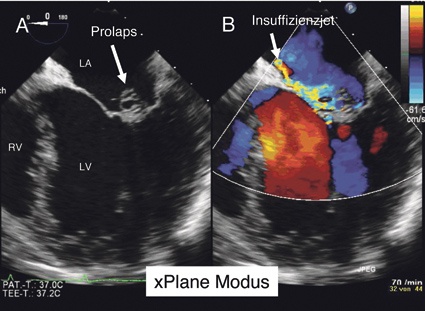

1 „x-Plane" Modus (Abb. 1): Hier besteht die Möglichkeit, gleichzeitig verschiedene (meist zwei) Schallebenen zu untersuchen, die in einem wählbaren Winkel zu einander stehen (Abb. 1A). Während des x-Plane ist ein Zuschalten des Farbdopplers möglich (Abb. 1B), um eine zeitliche Zuordnung von Insuffizienzjets zu anatomischen Strukturen in zwei Ebenen zu ermöglichen.

Am Beispiel eines jungen Patienten mit Palpitationen möchten wir den Stellenwert der dreidimensionalen Echokardiografie darlegen. Die primäre transthorakale 2-D-Echokardiografie war aufgrund von schlechten Schallbedingungen nicht aussagekräftig, sodass die Indikation zur transösophagealen Echokardiografie bestand. Im Rahmen der 2-D-TEE Untersuchung im x-Plane-Modus konnten eine systolische Vorwölbung bzw. eine abnorme Protrusion des posterioren Mitralsegels (P2) nach atrial während der Ventrikelsystole mit exzentrischem Refluxjet im Farbdoppler nachgewiesen werden (Abb. 1), sodass die Diagnose eines Mitralklappenprolaps gestellt wurde. Zur weiteren räumlichen Zuordnung und Größenabschätzung des Mitralklappenprolaps erfolgte die 3-D-TEE-Untersuchung (Abb. 2 und 3), bei welcher der 2-D-TEE-Befund bestätigt werden konnte. Anhand der dreidimensionalen Darstellung war erstmalig eine genaue Größenzuordnung und Lagebestimmung des Prolapes möglich, sodass in Zusammenschau aller Befunde die Indikation zur herzchirurgischen Mitralklappenrekonstruktion gestellt wurde. Anhand dieser Falldemonstration erklärt sich gerade die Stärke der 3-D-Echokardiografie, da es dadurch gelingt, die komplexe sattelförmige Geometrie der Mitralklappe in einem plastischen Gesamtbild zu veranschaulichen. Der interventionell tätige Kardiologe und der Kardiochirurg erhalten zum einen eine orientierte Pathomorphologie in Echtzeit und zum anderen eine räumliche Beziehung zwischen prolabierenden und nicht prolabierenden Mitralsegelsegmenten.